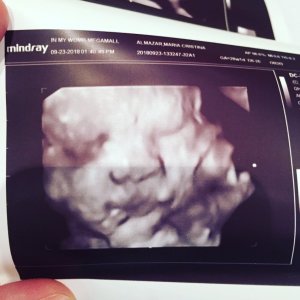

And he’s perfectly healthy and normal. No deformities detected. He was the perfect size for his age, what a relief. Also, we got the 4D pictures. The colored ones will be sent out much later but we got the black and white copies the same day!

Remember how freaky Damy looked in his initial 4D picture? Well, what a difference a few weeks make! His face (and whole body, apparently) filled out nicely. He’s a chubby little siopao now! My husband got his wish, Damy looks just like me. I wish he’ll take after his father’s temperament though, ahahhaha!